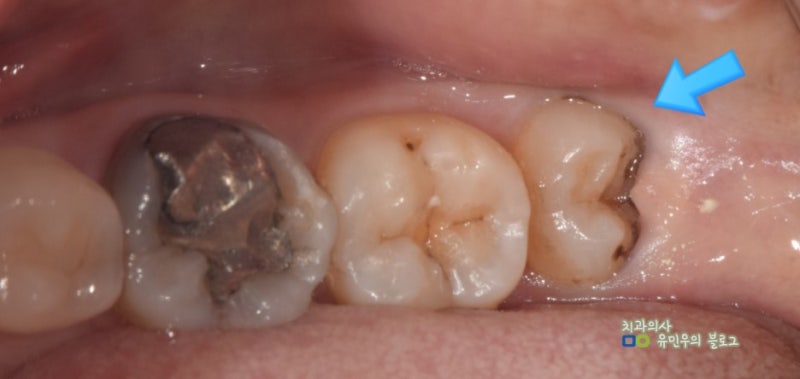

양쪽 아래 사랑니를 보면 맹출 방향이 역방향임을 알 수 있다. 사랑니를 앓는 환자들이 나중에 치과에 와서 사진을 보고 설명을 하면 치아가 수평이 아닌 것을 다행이라고 생각하는 경우가 많다. 그러나 치아가 뒤를 향하고 있을 때는 뒤쪽의 턱뼈가 치아를 매우 강하게 지지하고, 앞쪽과 반대 방향, 즉 발치 방향이 되어 있어 장치 접근이 어렵다. 위의 경우 치아의 뿌리도 많이 휘어져 있고 치아가 매우 커서 치아를 발치하기 어려운 상황에 해당합니다. 이 부분은 환자에게 치아발치를 했다고 충분히 설명을 드렸는데요, 위의 예에서는 사진상으로 양쪽 아래 사랑니와 오른쪽 위(실제로는 왼쪽 위) 사랑니를 포함하여 2~3개의 사랑니를 발치하였습니다.

사진 왼쪽 하단에 있는 사랑니였는데 뿌리가 휘고 머리가 너무 커서 치아가 여러 조각으로 쪼개져 뽑혔습니다. 치근이 뼈에 단단히 부착되어 발치가 어려웠지만 치근을 포함한 모든 치아가 깨끗하게 발치되었습니다. 사랑니 발치의 난이도는 엑스레이로 대략적으로 예측할 수 있지만 실제로는 치아 뿌리의 유착 정도와 환자 뼈의 경도도 중요하기 때문에 발치에는 실제로 시간이 걸린다. 시기에는 약간의 차이가 있을 것입니다. 골드내추럴치과에서는 다양한 사랑니 발치 경험 사례를 통해 가장 빠르고 불편함이 적은 사랑니 발치를 위해 노력하고 있습니다. 공포감이 강해 사랑니 발치를 미루게 되면 나중에는 염증으로 인해 발치시 더 큰 불편함을 유발할 수 있으며 앞니에도 악영향을 미칠 수 있습니다. 이는 보통 사람들이 걱정하는 것과는 다르고, 평소에 쉽게 할 수 있는 일이니 두려워하지 마시고, 다른 치아에 염증이 생기거나 다른 치아 건강 문제로 진행되기 전에 적절한 상담과 치료를 통해 치아 건강 문제를 보호하시기 바랍니다. .나는 희망